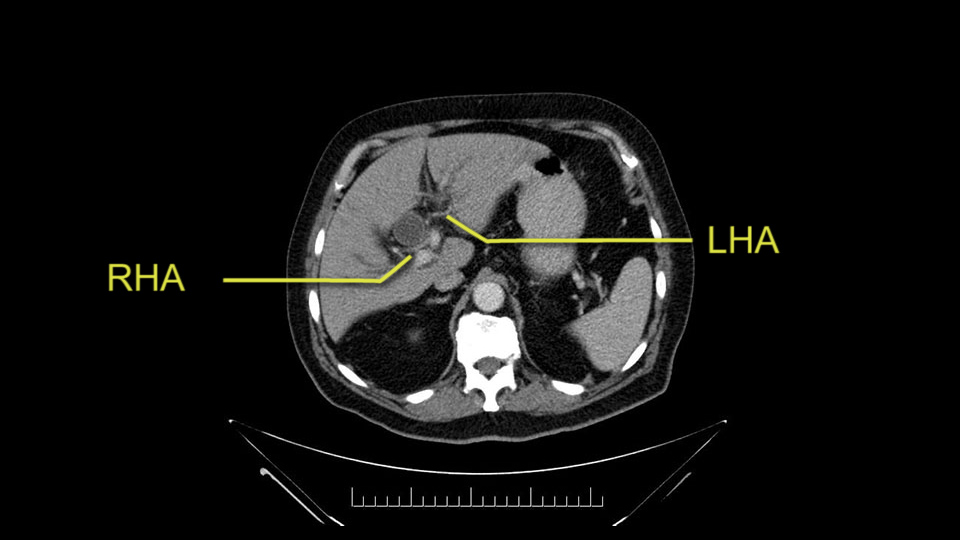

Then you look for anomalies. The one you worry about the most doing a Whipple is a replaced or aberrant right hepatic artery coming off the SMA at its origin. So again, find the SMA. You can find it because the renal vein goes through it. Follow it up, up-up-up. Nothing coming off of there that I can see here. Nothing coming off of it, nothing coming off of it and just to confirm it, look at the celiac trfurcation. There’s the celiac, there’s the bifurcation, there's the splenic artery, hepatic artery. Make sure there’s a right, which there is here. The right usually goes under the bile duct: important when you’re going around the bile duct to do a Whipple. A replaced right goes under the portal vein and the bile duct way over here on the right. That’s about it.

To plan a pancreatoduodenectomy, we start by reviewing the vascular anatomy, especially the origin of the celiac trunk, here, in front of the aorta, looking for any evidence of stenosis. In addition, we look at the origin of the superior mesenteric artery, to look for any branches, and any replaced right hepatic arteries coming from the superior mesenteric artery; which does occur in about 12% of the population.

The second point about the vascular anatomy-, is to again look for right hepatic arteries in the hilum, coming from the superior mesenteric artery by palpating-through the Winslow Hiatus. Usually we will check for a pulse in the posterior aspect of the hepatic hilum, where a right hepatic artery should not usually be found. In this case, the precaution is to avoid an accidental ligation of the right hepatic artery that might jeopardize perfusion of the right lobe, or if there is a completely replaced hepatic artery that can put the liver circulation at risk.

I am a believer in pylorus preservation. And in this case I see no reason why that wouldn't be possible. Mobilize the duodenum, divide the gastroepiploic vessels and divide the duodenum. I try to divide it with a linear stapler about four centimeters from the pylorus to have adequate length for my GI anastomosis. This facilitates exposure of the head neck of the pancreas. I find the gastroduodenal artery. This patient has normal arterial anatomy. Always on every preoperative CT scan I look to see if there is a replaced right hepatic. In this case I did not see one. Regardless of how confident I am I always look carefully for variant anatomy. I always do a clamp test on the GDA before ligation. I doubly ligate the GDA with not just a tie but a suture ligature because of the risk of GDA blowout in patients with a leak.